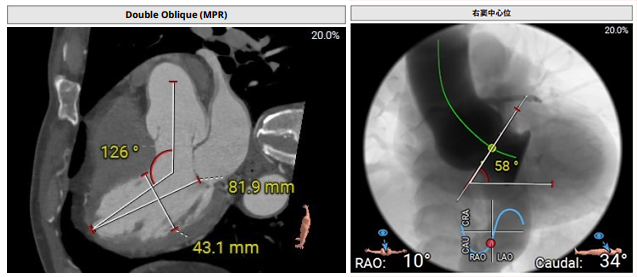

术前影像评估提示,患者主动脉为三叶瓣,无明显钙化,瓣窦分布不均。主动脉瓣环直径28.8mm,左心室流出道直径28.0mm,冠脉开口高度充足(左冠20.4mm,右冠21.4mm),左室与主动脉夹角126°。

CTA评估(上下滑动查看更多照片)